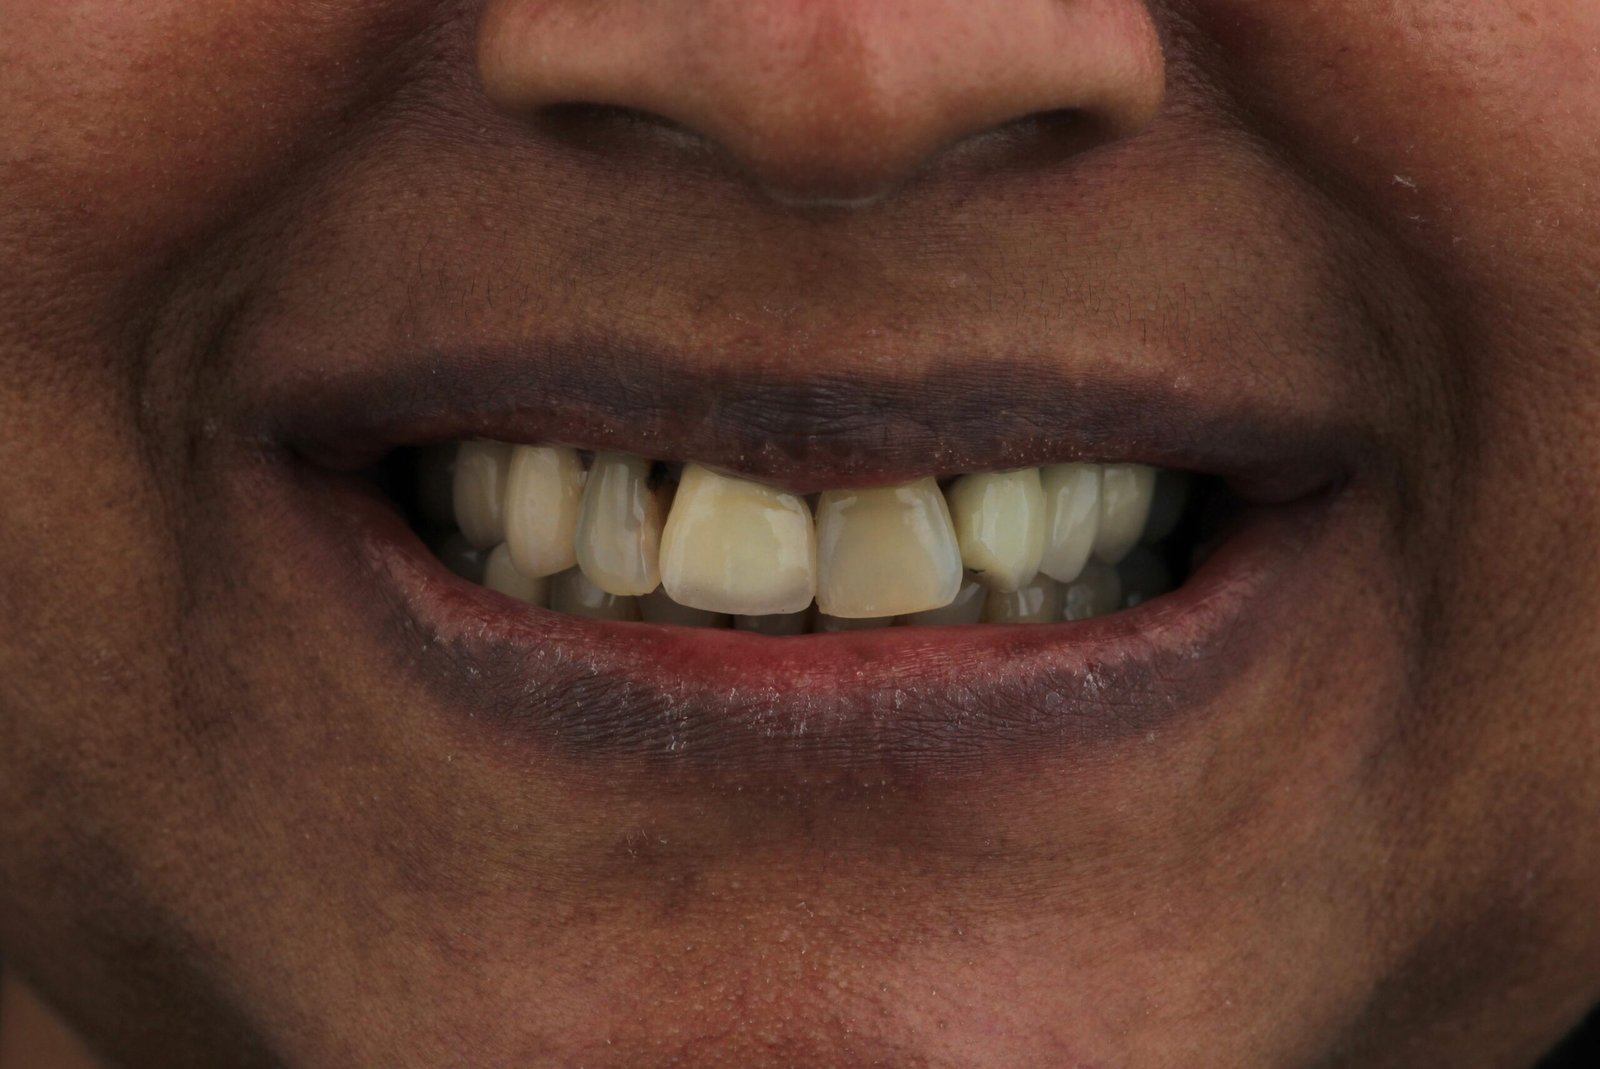

O que é o branquamento dentário?

O branqueamento dentário é um tratamento estético que clareia a cor dos dentes, devolvendo um sorriso mais luminoso, saudável e jovem. É seguro, eficaz e totalmente personalizado.

Quais as causas dos dentes manchados?